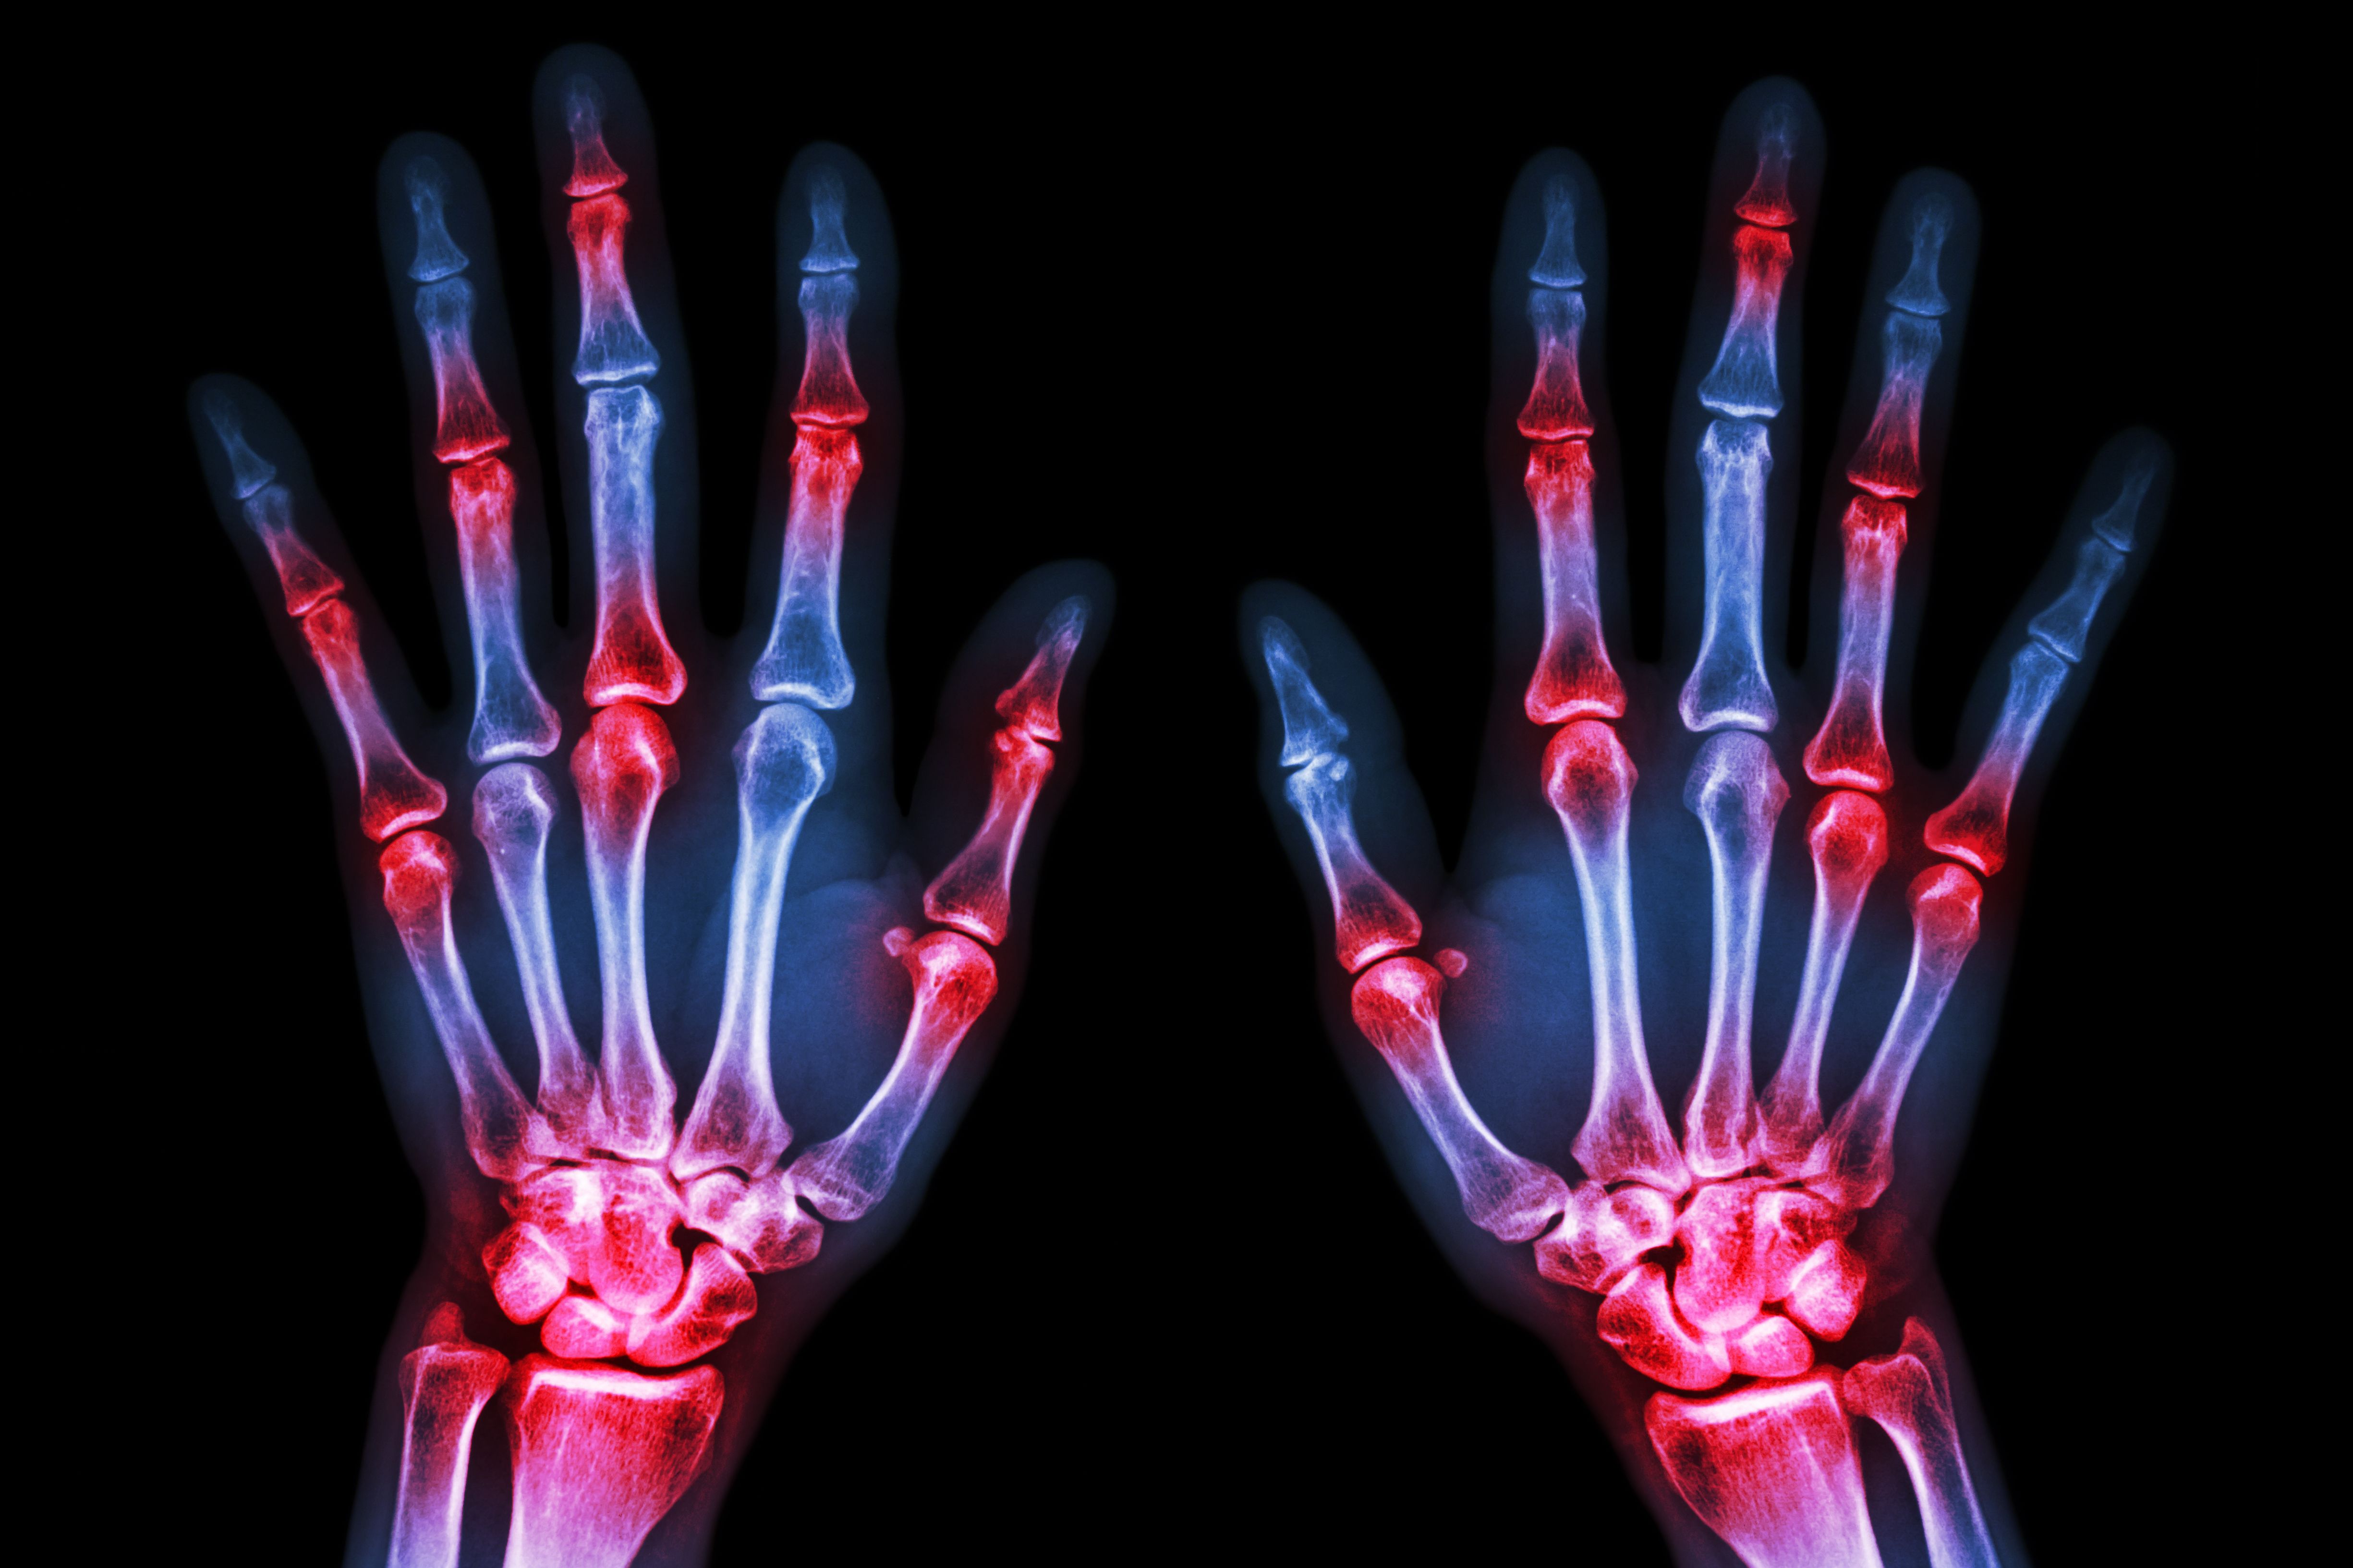

Rheumatoid arthritis is a common inflammatory joint disease. A feature of this disease is the increased fusion of endogenous immune cells (macrophages) to form so-called osteoclasts, which attack and break down bone tissue.